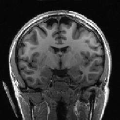

To compare the proposed approach to the mSENSE333SENSE reconstruction implemented by the Siemens scanner, software ICE, VB 17. one, Fig. 1 illustrates coronal anatomical slices reconstructed with both algorithms while turning off the temporal regularization in 4D-UWR-SENSE, so resulting in the so-called 3D-UWR-SENSE approach. Red circles clearly show reconstruction artifacts and noise in the mSENSE reconstruction, which have been removed using our 3D-UWR-SENSE approach. Comparison may also be made through reconstructed slices for and , as well as with the conventional acquisition (). This figure shows that increasing generates more noise and artifacts in mSENSE results whereas the impact on our results is attenuated. Artifacts are smoothed by using the continuity of spatial information across contiguous slices in the wavelet space. Depending on the used wavelet basis and the number of vanishing moments, more or less (4 or 8 for instance) adjacent slices are involved in the reconstruction of a given slice. For instance, using Symmlet filters of length 8 (4 vanishing moments) as in the conducted experiments here, 8 adjacent slices are involved in reconstructing a given slice. However, it is worth noticing that the introduced smoothing is anisotropic, in contrast to standard Gaussian smoothing that could be applied to anatomical data. Fig. 1 also compares 3D-UWR-SENSE and mSENSE reconstructed slices when applying additional spatial smoothing to the later with a mm3 Gaussian kernel. Comparisons clearly show that, even at such low spatial smoothing level, mSENSE images suffer from a significant blur. Moreover, the artifact present at for mSENSE (left red circle) is spread out but not fully removed by applying isotropic spatial smoothing.

Even for slice-selective acquisition schemes where the signal is supposed to be independent between adjacent slices, the proposed algorithm still allows us to exploit information continuity across slices which results from the imaged anatomy. Moreover, the smoothing level strongly depends on the regularization parameters that are used to set the thresholding level of wavelet coefficients. Images reconstructed using our algorithm present higher smoothing level than mSENSE without altering key information in the images. When carefully analysing the image background, one can notice the presence of motion-like artifacts that only affect the background and do not alter the brain mask. Such artifacts are nothing but boundary effects that are due to the use of wavelet transforms.